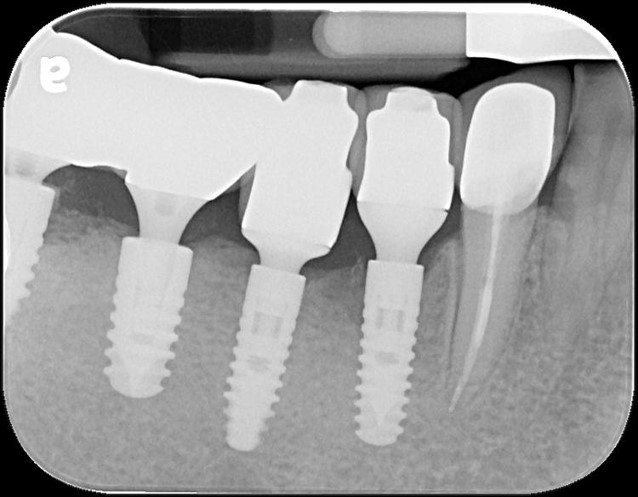

術後X光

治療後X光,穩合度良好